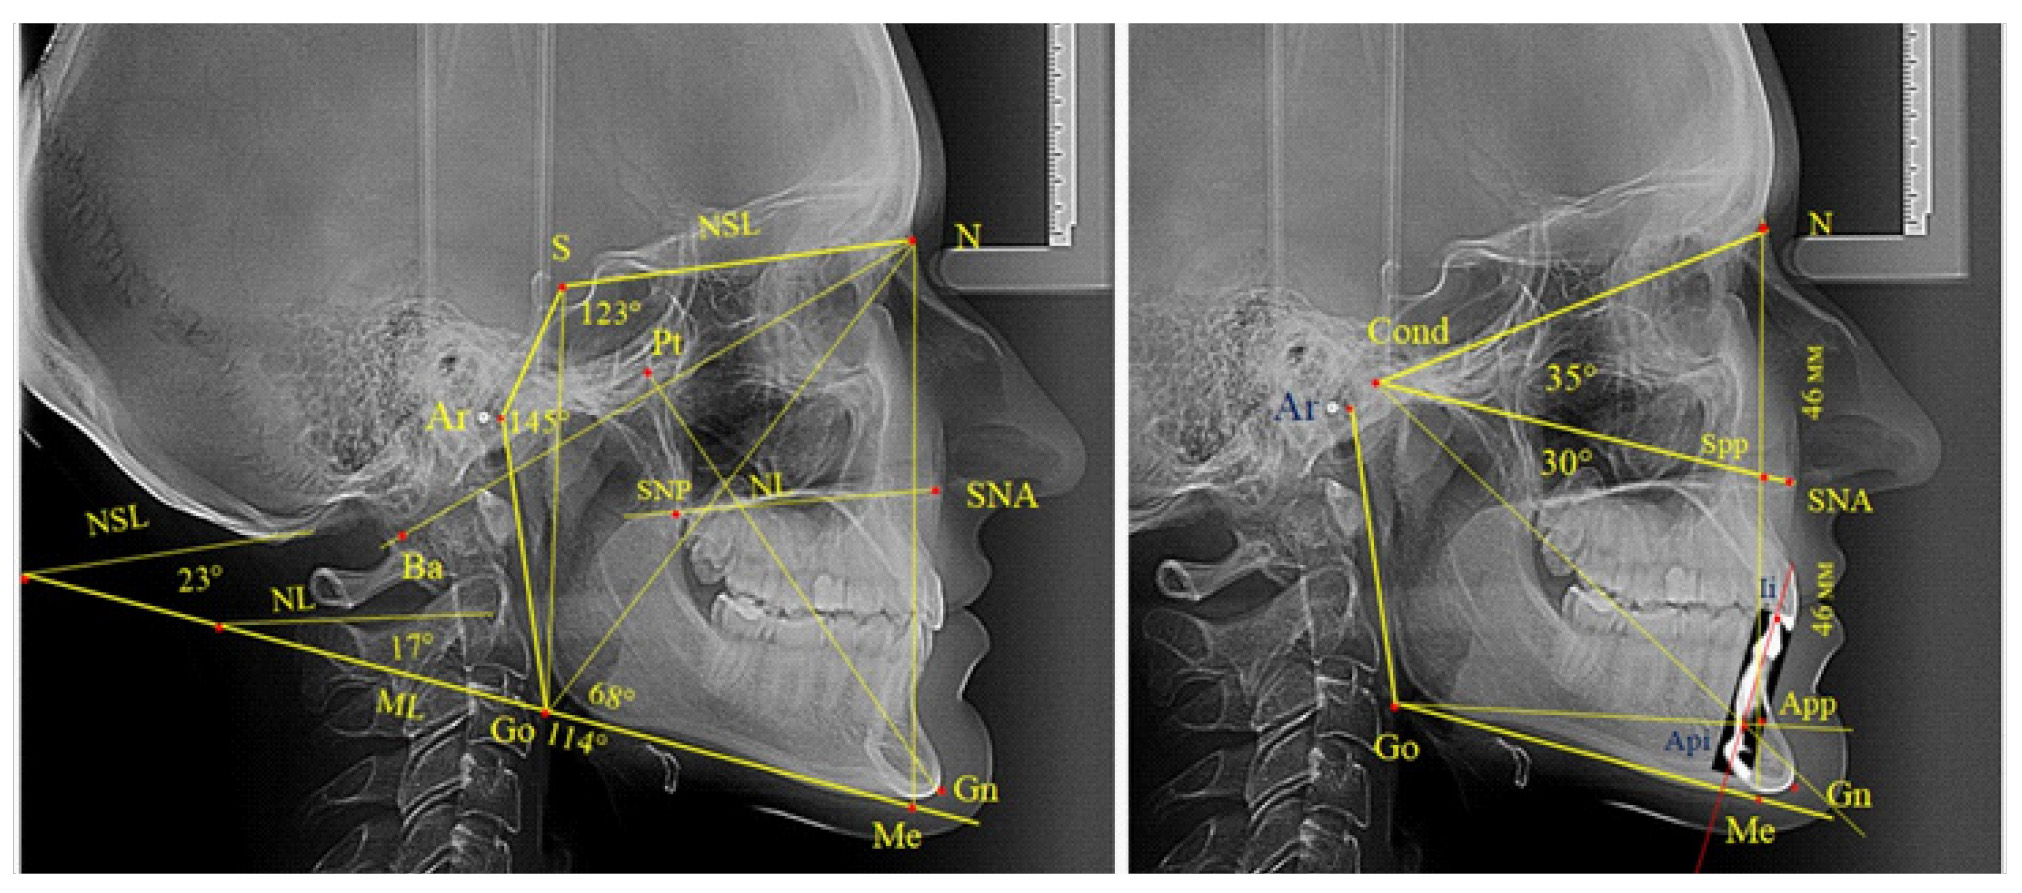

Основу анализа традиционно составляла суммарная составляющая трех углов Bjork, которая включала углы N-S-Ar, S-Ar-Go и Ar-Go-Me, которые ограничивают костные структуры линевого отдела головы, и полученная величина определяет типологические особенности роста лица. Нижний нижнечелюстной угол образован линиями N-Go и Go-Me. При построении лицевого угла Ricketts проводили линию N-Ba и линию Pt-Gn, с последующим измерением внутреннего угла.

Также к показателям типа роста относили углы, образованные мандибулярной плоскостью, с линией основания черепа (NSL-ML) и основания верхней челюсти (NL-ML). Кроме определения угловых параметров оценивали линейные показатели, в частности проводили сравнение передней высоты лица (N-Me) с задней высотой (S-Go).

Нередко при анализе телерентгенограммы на верхушку корня медиального нижнего резца наслаиваются контуры соседних зубов, и данный ориентир недостаточно четко определяется. В подобных случаях выделяли фрагмент зуба из томограммы с последующим наложением и совмещением с телерентгенограммой.

Данная методика позволяла определять положение верхушки корня медиального нижнего резца, полученный ориентир в ортодонтии принято обозначать как Api (apicalе inferior), а точка режущего края нижнего резца обозначалась как Ii. Для оценки вертикальных параметров оценивали угол N-Cond-SNA, который использовали для определения параметров назального отдела. При этом точка Cond соответствовала верхнему полюсу суставной головки. Угол SNA-Cond-Api определял угловые параметры гнатического отдела лица без учета размеров подбородка, который является наиболее вариабельной структурой нижней челюсти. Альвеолярную часть нижней челюсти отделяли от подбородочной части линией, соединяющей конструктивную точку угла нижней челюсти Go с верхушкой корня нижнего резца (Go-Api).

Вертикальная линия передней высоты лица (N-Me), после ее пересечения с линией Cond-SNA, определяла положение точки Spp, при этом вертикаль N-Spp использовалась в качестве оценки высоты назального отдела лица. Продолжение линии Go-Api до пересечения с линией N-Me позволяла определить положение конструктивной точки Арр и оценить линейные размеры гнатической части лица по величине вертикали Spp-Арр (рис. 1).

Рис. 1. Методы оценки основных параметров ТРГ для определения вертикальных размеров лицевого отдела головы